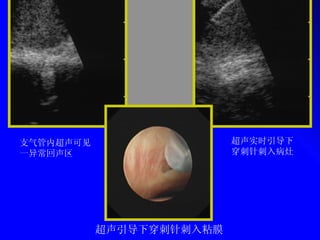

ę”Æę°”ē®”å†…č¶…å£°åÆč§äø€å¼‚åøøå›žå£°åŒŗ č¶…å£°å¼•åÆ¼äø‹ē©æåˆŗé’ˆåˆŗå…„ē²˜č†œ č¶…å£°å®žę—¶å¼•åÆ¼äø‹ē©æåˆŗé’ˆåˆŗå…„ē—…ē¶

Bronchoscopic View of a Transbronchial Needle  Aspiration of a Subcarinal Node Herth FJ. Eur Respir J 2006

(BF-UC160F-OL8; Olympus Medical Systems, Tokyo, Japan) Linear Real-time Endobronchial Ultrasound-guided  Transbronchial Needle Aspiration Scope

(BF-UC160F-OL8; Olympus MedicalSystems, Tokyo, Japan) Linear Real-time Endobronchial Ultrasound-guided Transbronchial Needle Aspiration Scope